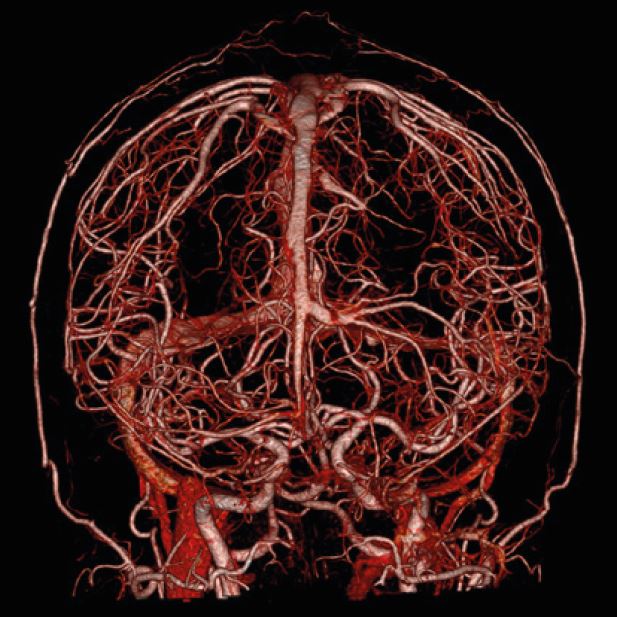

Наші КТ-сканери та програмне забезпечення для постобробки здатні створювати тривимірні зображення з високою роздільною здатністю, що, по суті, усуває попередні проблеми, пов’язані з візуалізацією перфузії. Обмеження часткового охоплення мозку КТ-перфузією було подолано завдяки введенню зонального детектора на Aquilion ONE та режиму "shuttle mode" в Aquilion Prime SP.

SURESubtraction